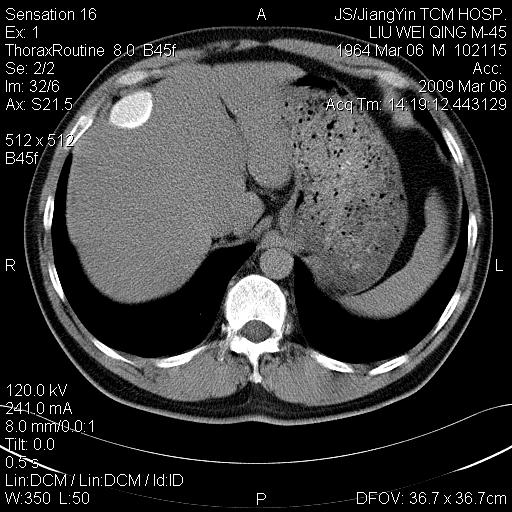

标题: CT18518:胸部扫描时发现肝边缘钙体影。请问是韧带钙化吗? [打印本页]

标题: CT18518:胸部扫描时发现肝边缘钙体影。请问是韧带钙化吗?

没见过。考虑肝内钙化,不象韧带钙化。

考虑肝内右外侧缘两处钙化,原因呢?(血管病变或其它)

考虑肝包膜下陈旧性包裹性积液。

考虑---局限性腹腔积液〔钙乳性〕。    一般多为炎症刺激造成局部钙乳沉着所致。

考虑肝包膜下钙化

考虑肝包膜下钙化.